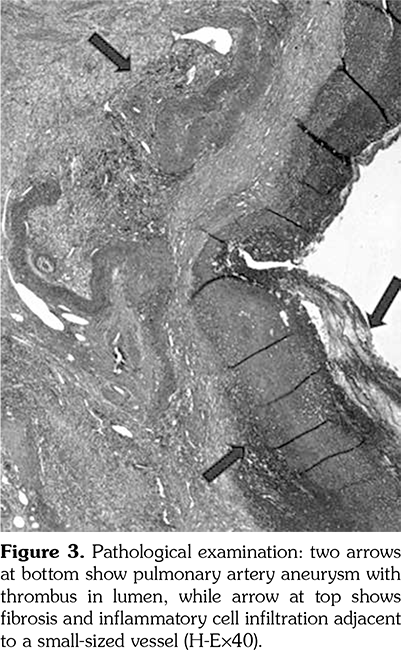

Chest X-ray showed retrocardiac hyperdensity on admission (Figure 1). Diagnostic investigations for tuberculosis were all negative. On bronchoscopy; left lower lobe bronchus was narrowed due to the external compression and abundant viscous secretions were observed. Computed tomography (CT) angiography was performed, which was consistent with multiple PAAs bilaterally (Figure 2). Diagnostic investigations such as echocardiogram and lower extremity venous Doppler ultrasonography, renal function evaluation, eye examination, abdominal ultrasound, and rheumatologic tests revealed no pathological findings. Our patient’s investigational tests for PAA were negative for cardiovascular disease, pulmonary hypertension or any infection.